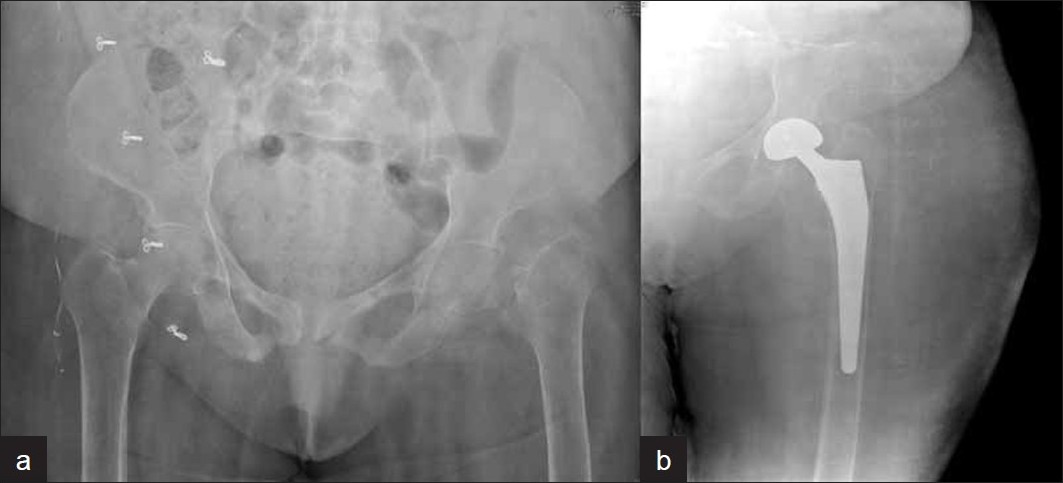

Giriraj orthopedic trauma surgeons offer treatment for these unplanned, critical events - major and minor fractures, nerve and tendon injuries, joint dislocation and other orthopedic injuries. Our surgeons provide expert, compassionate care for patients and their families in these emergencies, beginning with new, less invasive techniques for highly specialized reconstructive surgeries. As a Level One Trauma Center, Giriraj Hospital provides the highest level of emergency care in with state-of-the-art facilities and services. Our orthopedic surgeons are fellowship-trained and experts in orthopedic surgery, so our patients receive highly specialized emergency and follow-up care.

Additionally, Giriraj Hospital's high-tech imaging and surgical equipment can give patients and families choices in their treatment or therapy. For example, depending on the injury, patients may have surgical, medicinal or therapeutic options - or a combination of all three types of therapy. Our experienced Giriraj Hospital trauma team to provide comprehensive care to acutely injured patients. This multidisciplinary team includes general surgery trauma surgeons, nursing staff, mid-level providers and therapists.